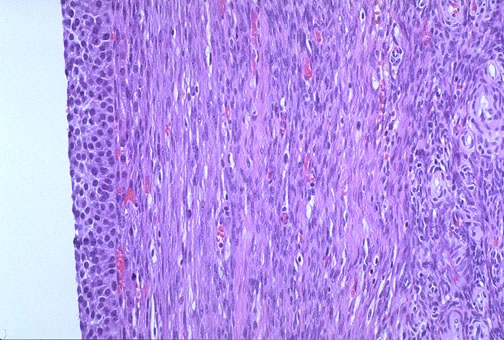

This is a benign theca lutein cyst in an ovary. Note the luteinized cells forming the inner cyst lining at the left, with adjacent surrounding theca cells. These cysts are rarely more than a few centimeters in diameter.